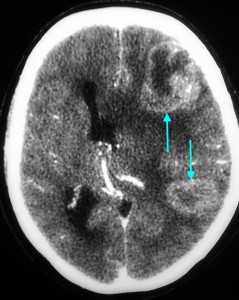

Метастазы головного мозга, фото. На КТ с контрастным усилением у пожилой пациентки (в верхнем ряду слева) с жалобами на головные боли выявлены множественные объемные образования в левом полушарии мозга, интенсивно накапливающие контрастное вещество. Образования имеют характерную форму в виде «кольца». На изображениях в нижнем ряду и вверху справа определяются множественные очаги в головном мозге: отчетливо видны округлые образования с более плотным «ободком» по периферии, располагающиеся в левой теменной доле.